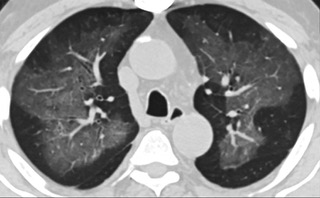

疑點一,電子煙患者的CT影像和臨床表現(xiàn)并不具有特異性。所謂美國電子肺炎患者,其實是對沒有其他合理診斷證據(jù)、吸食電子煙肺炎患者的統(tǒng)稱。這些患者在病發(fā)前90天內(nèi)吸食了電子煙,尤其值得注意的是,部分患者的CT影像特征和臨床表現(xiàn)與病毒性肺炎患者極其相似。

疑點二,中國科研工作者從60篇研究論文中篩選出142位電子煙肺炎患者的250張影像圖片,邀請3位放射科權威專家,對上述全部影像圖片、相關病人臨床信息以及文獻原文進行了仔細全面研究與審查,又有了新的發(fā)現(xiàn)。